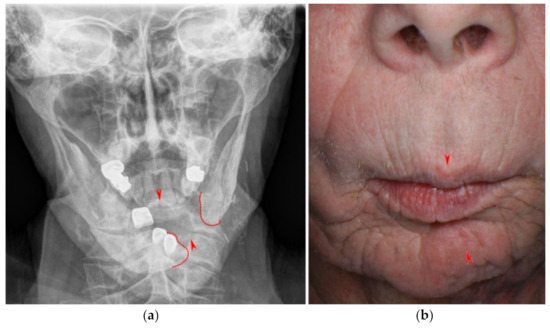

Partial mandibular resection with complete transection of the mandibular bone without reconstruction will lead to mandibular dislocation and functional asymmetry (Figure 8 and Figure 9). Radiation and scarring may even increase structural and functional asymmetry. Therefore, surgical reconstruction of the mandible is the therapy of choice whenever it is possible [123].

Figure 8.

Anteroposterior radiograph (a) and aspect of a male patient (b) suffering from oral cancer of the tongue and mandible. After tumor surgery and radiation therapy, the mandibular bones were connected by a reconstruction plate. Following local infection, reconstruction was no longer possible and, therefore, a gap between the right and left mandible remains on the patient’s left side (red dotted lines). Arrows indicate upper and lower jaw midline.

Figure 9.

Panoramic radiograph of the same patient three years later after further tooth loss.